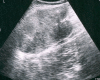

Case presentation: The case of a desmoid tumor of the anterior abdominal wall in a 40-year-old Caucasian man with no relevant family history is presented, describing its appearance on computed tomography and ultrasonography. The patient, who presented with a painless mass in the left anterolateral abdomen, had a history of previous urgent abdominal surgery after a shotgun injury two years earlier. Radical resection of the affected abdominal wall musculature was performed, and the defect was reconstructed with polypropylene mesh.